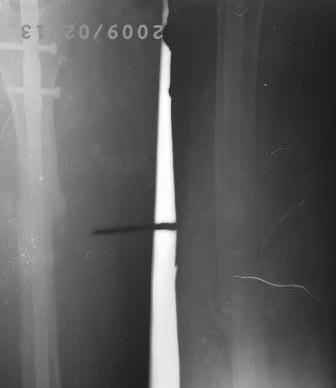

Снимки не очень качественные, почему-то все снимки такие . видимо поступило партия некачественных пленок.

12.02.09г б-ная оперирована: з/остеоклазия (без особого труда- видимо тугой ложный сустав) коррекция деформации, удаление штифта из надвертельной обл, рассверливание канала гибкими развертками, реостеосинтез блокируюшим гвоздем Д-11мм.

P.S. Снимки не качественные, извиняюсь! последний снимок ЭРГА, два снимка объединил.